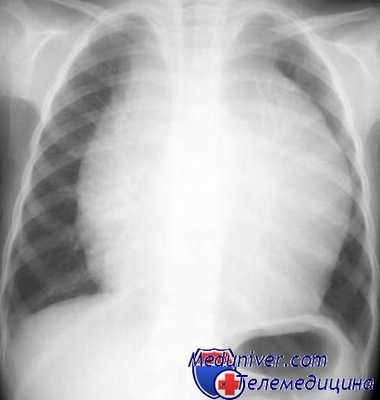

Больная лимфогранулематозом. Рентгенограмма грудной клетки в прямой проекции.

Расширение средостения в верхнем этаже за счет увеличенных лимфатических узлов.